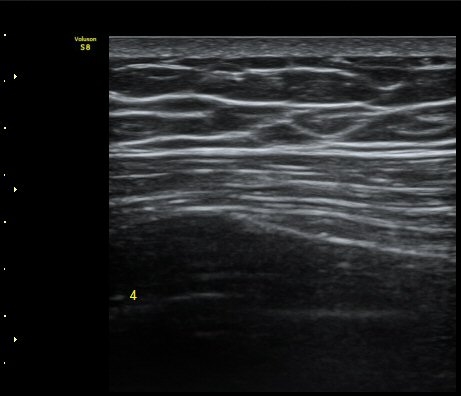

ÃÊÀ½ÆÄ °Ë»ç

¹Ì¼¼ÇÏ°Ô °¥ºñ»À ÇÇÁú°ñ ¿¬°á¼º ¼Ò½Ç°ú ¿¬ºÎÁ¶Á÷ ºÎÁ¾ÀÌ °üÂûµÊ(loss of cortical continuity and soft tissue swellingof rib)   »çÁø 1, 2, 3

3, 4,, 5 ¹øÂ° °¥ºñ»À °ñÀýÀÌ È®ÀεÊ.

°¥ºñ»ÀÀÇ ¹Ì¼¼°ñÀýÀº ´Ü¼ø¹æ»ç¼±ÃÔ¿µ¿¡¼­ º¸ÀÌÁö ¾Ê´Â´Ù. º» Áõ·Ê¿¡¼­ ¿¢½º·¹À̰˻翡¼­´Â °ñÀýÀÌ È®ÀεÇÁö ¾Ê¾ÒÁö¸¸

ÃÊÀ½ÆÄ°Ë»ç¿¡¼­´Â °¥ºñ»À 3°³ÀÇ ¹Ì¼¼ °ñÀýÀÌ È®ÀεǾú´Ù.